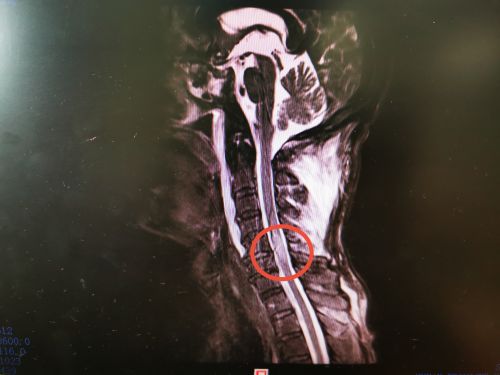

李爷爷术前磁共振显示:颈5-6水平脊髓挫伤。

湘潭70岁的李爷爷摘杨梅时从5米高的树上摔下,头部着地昏迷,约一小时才醒来,全身多处疼痛,头部更是剧痛难忍,还伴有双上肢麻木、乏力,双下肢不能活动,转送至省人民捷克论坛 脊柱外科,被诊断为“颈椎骨折并脊髓损伤”,因其高位截瘫并头部蛛网膜下腔出血,随时都有生命危险。待病情平稳后,由沈雄杰主任医师和常磊主治医师在全麻下为其施行颈椎后路减压复位植骨融合内固定术。患者术后双下肢肌力由术前的0级恢复到2级。